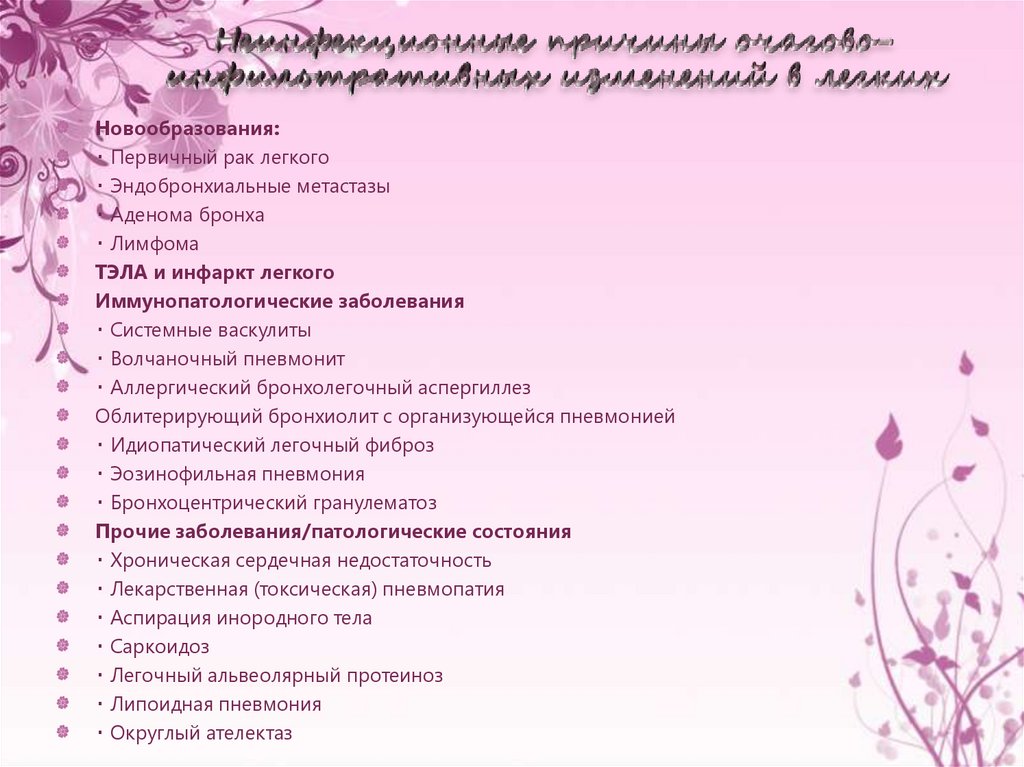

Острая внебольничная пневмония по МКБ-10: признаки и примеры